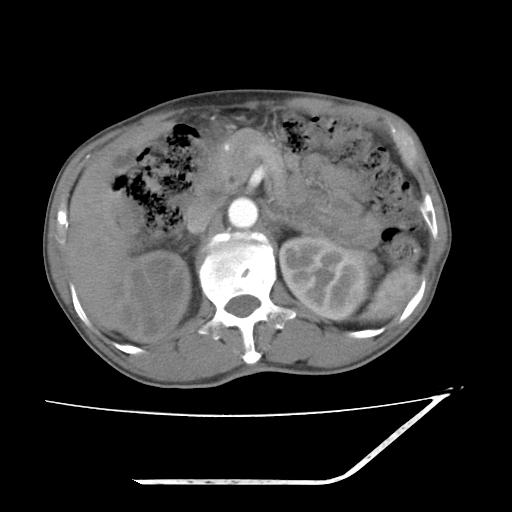

增强

考虑右肾盂癌,肾动脉受侵,右肾功能减退,右肾盂输尿管积水,管壁增厚,考虑种植转移,应该把下面扫完的

支持右侧肾盂癌伴肾静脉瘤栓形成可能性大,右肾结石.肝右叶后段低密度影,不除外转移.

考虑右肾盂癌,肾动脉受侵,右肾功能减退,右肾盂输尿管积水,管壁增厚,考虑种植转移  支持

右肾盂旁ca并肾静脉瘤栓形成/肾功能降低。

右肾结石。

右肾盂癌,肾动脉受侵,右肾盂输尿管积水,管壁增厚,考虑种植转移

右肾盂移行细胞癌并右输尿管中段转移.肾积水.

支持 右侧肾盂癌伴肾静脉瘤栓形成可能性大,右肾结石;肝右叶后段低密度影,不除外转移。

1.右侧肾盂癌伴肾盂积水。

2.肾脏功能减退,原因有:(1)肾动脉受侵。(2)肾静脉受侵(3)肾积水,等。本例,肾动脉显影较好,但受压明显;肾静脉无明显显示,受压或静脉癌栓,下腔静脉腔内未见明显充盈缺损。

3.右侧上段输尿管扩张,原因:(1)积水所致;(2)种植。